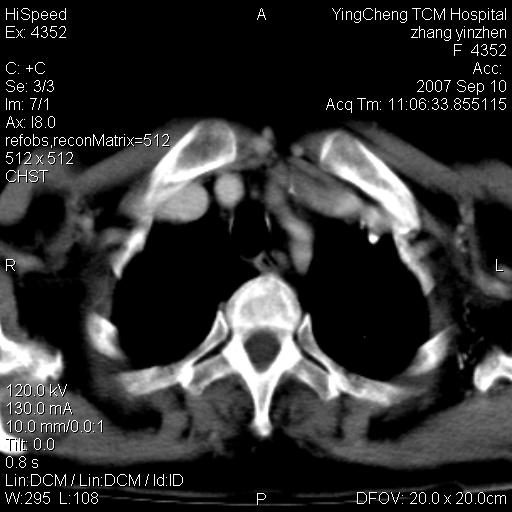

以下是引用卜一在2007-9-18 14:41:00的发言:[br]右肺肿块:毛刺+胸膜凹陷征+供血血管+浅分叶+强化。支持:周围性肺癌 !另:左侧甲状腺腺瘤!

以下是引用夏季在2007-9-18 11:00:00的发言:[br]1。右肺肿块,周围有短毛刺,肺门侧有血管与其相连,胸壁侧有胸膜凹陷征,考虑周围性肺癌 2。左侧甲状腺软组织肿块,内有高密度钙化灶,考虑左侧甲状腺腺瘤。